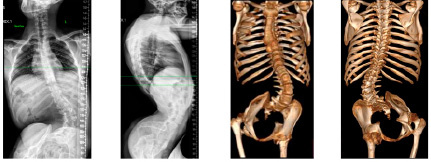

Сколиоз является одним из наиболее распространенных патологических состояний, по поводу которого проводят инструментальную фиксацию позвоночника. Независимо от этиологического фактора сколиотические деформации сопровождаются не только отклонением оси позвоночника, но и изменениями формы и размеров структур позвонков, их ротацией и торсией.

Цель операции при сколиозе — коррекция деформации для сбалансированного положения позвоночника и предотвращения прогрессирования искривления [1, 2].

Установка винтов является одним из наиболее сложных аспектов хирургии позвоночника из-за риска неправильного размещения с повреждением спинного мозга, нервных корешков, расположенных рядом внутренних органов, а в дальнейшем — миграции и переломов имплантов [3].

По данным послеоперационной компьютерной томографии (КТ), частота мальпозиций винтов при оперативных вмешательствах по коррекции деформаций позвоночника составляет до 57,8 %. Осложнения, связанные с положением винтов, наблюдают в 0,64–1,1 % случаев, а неврологический дефицит — в 0,3–0,8 % [2, 4, 5].

Неправильное расположение транспедикулярных винтов и длительная продолжительность операции — две основные проблемы, которые негативно влияют на конечные результаты хирургических вмешательств при сколиозе [1, 4].